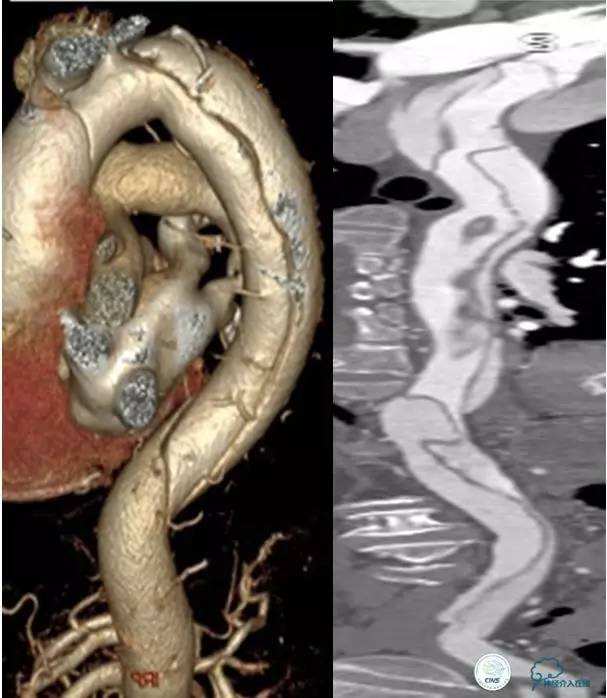

▼主动脉全程CT

诊断:

主动脉夹层 DeBakey Ⅰ型

短暂性脑缺血发作

急性心肌缺血

急性肾功能不全

急性肠系膜动脉缺血

中间诊断:

主动脉夹层 De Bakey Ⅰ型